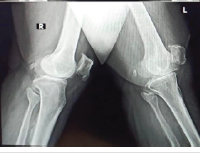

An active 21-year-old female sustained a right basicervical femoral neck fracture after being struck by a golf cart. She was treated at another institution using the FNS with an additional partially threaded headless screw (Fig. 2a and b). Seven months post-operatively, she developed progressive, atraumatic right hip pain with an inability to ambulate. She presented to our institution for evaluation. Radiographs demonstrated a right femoral neck non-union with implant failure through the bolt and antirotation screw at the level of the plate barrel aperture (Fig. 3a and b). She was consented for revision surgery with intertrochanteric valgus osteotomy and blade plate fixation.